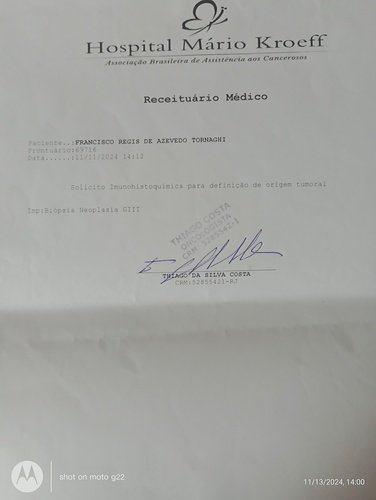

Me chamo Leidiane dos Santos Silva e estou criando essa vaquinha online para ajudar um amigo, pai e muito mais. Ele se chama Francisco Regis de Azevedo Tornaghi. Foi e ainda é uma pessoa que ajuda muitas pessoas e hoje ele está passando por uma fase muito difícil da sua vida. Agora ele está precisando muito da ajuda dos amigos para que ele possa realizar um tratamento de câncer de pele, o qual vem lutando desde o ano passado. Esse ano o câncer voltou e está progredindo de forma muito agressiva. Ele está sendo acompanhado pelo SUS mas o SisReg não dá conta de atender de imediato. Terá que fazer exames muito caros como: análise imunohistoquimico de origem tumoral, tomografia de face, pescoço e tórax. Hoje ele mora em Pedra de Guaratiba e está sendo acompanhado no Hospital MÁRIO KROEFF, na penha, muito longe de casa e fica difícil para a locomoção. Quando começar radioterapia e quimioterapia terá que ir todos os dias. Precisará fazer radioterapia todos os dias e quimioterapia 2 vezes na semana. Para ir de transporte público tem que pegar 4 conduções. Ele não aguenta pois tem 75 anos de idade.Por esse motivo estou aqui fazendo essa vaquinha para que os amigos e familiares possam colaborar com qualquer quantia para ajudar nesse momento muito difícil. Desde já agradeço a todos pela ajuda.